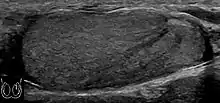

Teratoma Although teratoma is the second most common testicular tumor in children, it affects all age groups. Mature teratoma in children is often benign, but teratoma in adults, regardless of age, should be considered malignant. Teratomas are composed of all three germ cell layers, i.e. endoderm, mesoderm and ectoderm. At ultrasound, teratomas generally form well-circumscribed complex masses. Echogenic foci representing calcification, cartilage, immature bone and fibrosis are commonly seen [Fig. 5]. Cysts are also a common feature and depending on the contents of the cysts i.e. serous, mucoid or keratinous fluid, it may present as anechoic or complex structure [Fig. 6].

Fig. 5. Teratoma. A plaque-like calcification with acoustic shadow is seen in the testis.